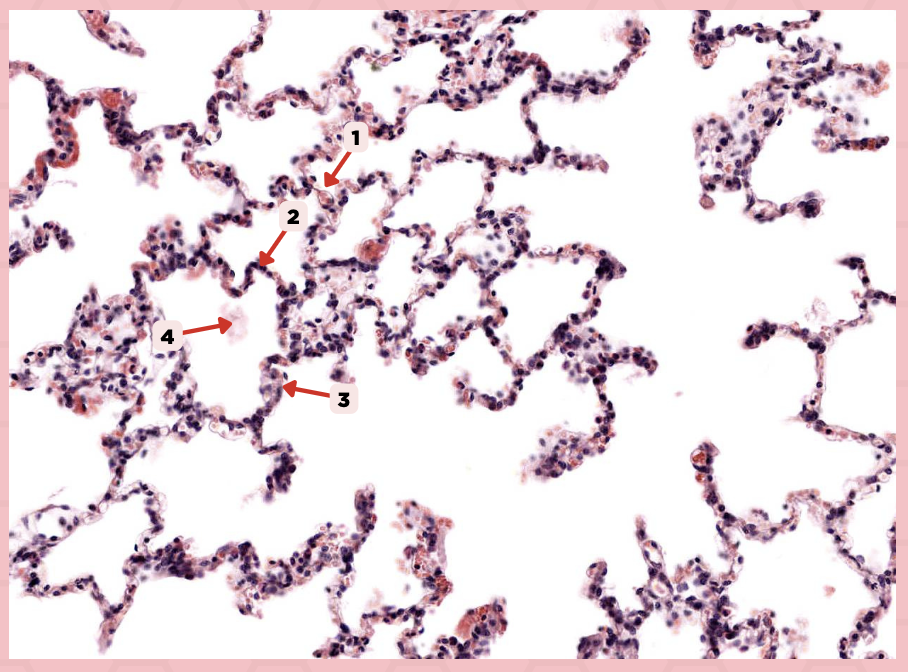

Interalveolar septum

Identify the structure labeled as 1.

Type I alveolar cell

Identify the structure labeled as 2.

Type II alveolar cell

Identify the structure labeled as 3.

Pulmonary Alveolar Macrophages (Dust Cells)

Identify the structure labeled as 4.

Pulmonary Alveolar Macrophages (Dust Cells)

What are the most numerous cells inside the alveoli?

Pneumocyte Type I

Which of the following labeled structures covers 95% of the alveolar surface?

Type I alveolar cell

Identify the structure labeled as 1.

Type II alveolar cell

Identify the structure labeled as 2.

Pulmonary Alveolar Macrophages (Dust Cells)

Identify the structure labeled as 3.

Endothelial Cells

Identify the structure labeled as 4.